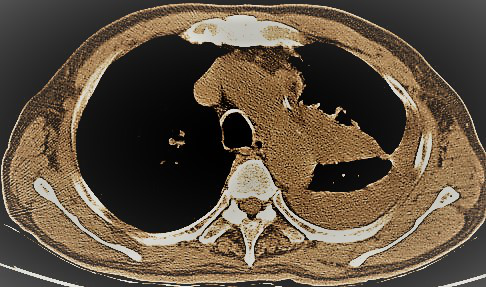

26 2021.12氣管鏡下姑息治療晚期肺癌

今日再次為一例肺部占位合并氣道內(nèi)腫瘤的患者施行支氣管鏡下的介入手術(shù),術(shù)前呼吸困難、心律失常二聯(lián)律,術(shù)后患者呼吸困難明顯緩解,且心律失常得以糾正,效果立竿見(jiàn)影。但是影像學(xué)的巨大腫塊,還需要結(jié)合病理分型采取恰當(dāng)?shù)木C合治療手段來(lái)……